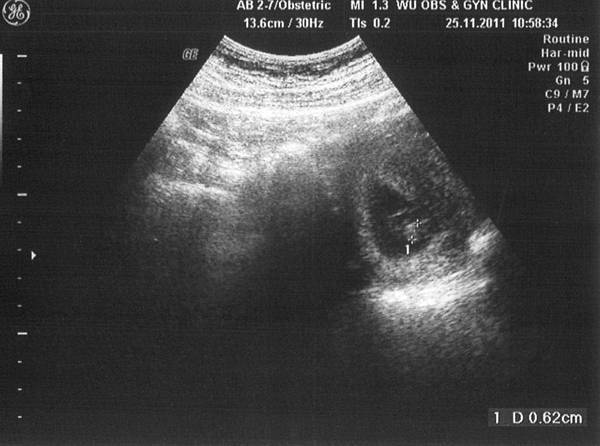

照超音波的過程也很輕率,醫生壓壓我的肚子,

就說「在右下腹,大概五週,兩個禮拜後來看有沒有心跳」,

然後就結束了=___=

不過看到肚子裡有小生命真是好奇妙

分明就是顆小肉球啊你~~